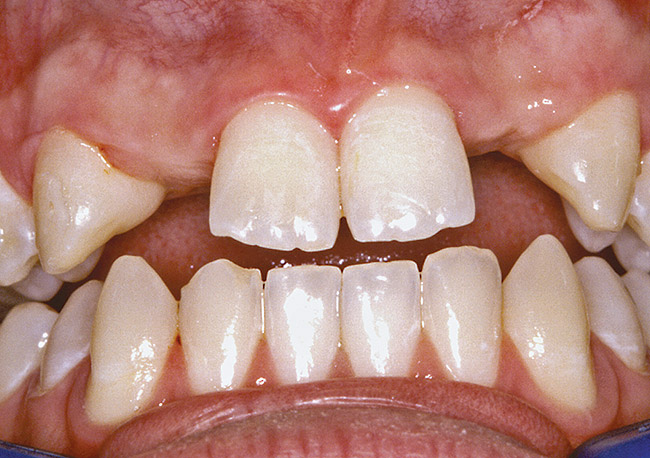

A 17-year-old boy presented with a history of congenitally missing maxillary lateral incisors. The patient had been under the care of an orthodontist for several years to manage his occlusion during his adolescent growth phase. The patient originally presented with his parents after being told that the “braces were ready to be removed, and their son was now ready for implants to replace the missing teeth.” This is not an uncommon circumstance, and unfortunately the orthodontic alignment was performed before the patient was sent to the restoring dentist. Therefore, the orthodontist was not aware of the space requirements for future implant placement. This case highlights the importance of proper communication between all members of the implant team, especially during the orthodontic planning phase. The patient’s medical history was unremarkable, and the patient was found to be healthy and a good potential candidate for dental implants to replace the missing lateral incisors.

Before the day of surgery, the patient was seen by the orthodontist for the removal of the orthodontic brackets. The patient still was not pleased with the position of the two centrals, and it was determined that this would be addressed after implant placement (Figure 26). The anatomical variations of the crestal tissue and lack of interdental papilla can be appreciated in the close-up views of the right and left sites (Figure 27 and Figure 28). There were no surprises on the day of surgery as all of the decisions were made during the planning phase, before the scalpel ever touched the patient. The occlusal view of the CT 3D model revealed the wider alveolar ridge on the right side and thinner crest on the left side (Figure 29). This was confirmed when the full-thickness mucoperiosteal flaps were elevated, and the underlying bone revealed (Figure 30). The tooth-borne templates were designed to facilitate the drills and drilling sequence specific to the diameters of the predetermined implants (Figure 31). Each template contained an embedded 5-mm long stainless steel tube, which was approximately 0.2-mm wider than each drill (just wide enough to allow for the drills to rotate freely). Once positioned over the natural teeth, the template was secure and offered precision accuracy in transferring the implant locations from the original software-designed plan, allowing the potential for internal and external irrigation (Figure 32).

Figure 26  VIRTUAL PLANNING AND SURGERY Before implant surgery, the orthodontic brackets were removed, revealing the position of the centrals, and the anatomical variations of the crestal tissue and lack of interdental papilla.

Figure 26

Figure 27   VIRTUAL PLANNING AND SURGERY Before implant surgery, the orthodontic brackets were removed, revealing the position of the centrals, and the anatomical variations of the crestal tissue and lack of interdental papilla.

Figure 27

Figure 28   VIRTUAL PLANNING AND SURGERY Before implant surgery, the orthodontic brackets were removed, revealing the position of the centrals, and the anatomical variations of the crestal tissue and lack of interdental papilla.

Figure 28